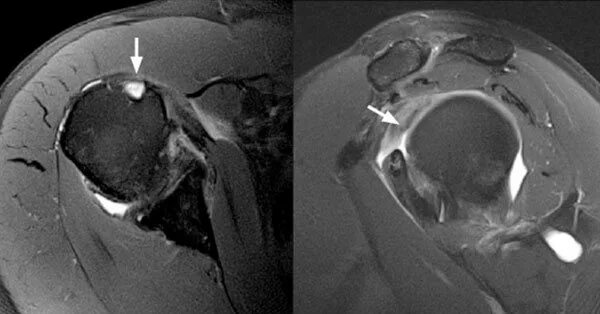

Разрыв длинных сухожилий